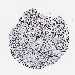

CANCER BREAST CANCER Show tissue menu

BRCA TCGA BRCA VALIDATION PROTEIN EXPRESSION

ANTIBODIES

AND

VALIDATION